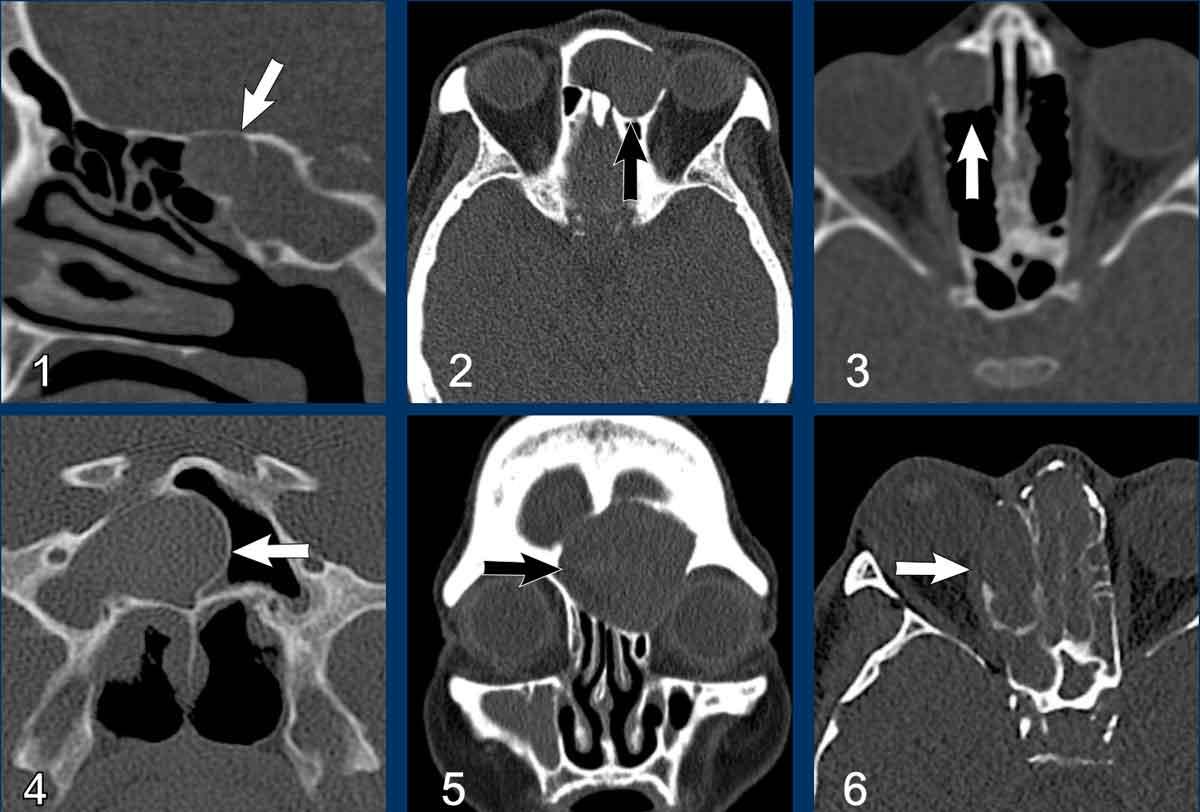

Dưới đây là thêm các ví dụ về nang nhầy.

- Nang nhầy nhỏ

ở xoang bướm.

Xoang bị lấp đầy hoàn toàn bởi mô mềm (tức là chất nhầy) kèm theo giãn rộng với bờ xương xoang còn nguyên vẹn. - Nang nhầy xoang trán.

Đôi khi, bờ xương bị mỏng đi có thể gây nhầm lẫn với phá hủy xương. Trên các lát cắt CT mỏng, thường có thể nhìn thấy cấu trúc xương còn nguyên vẹn. - Nang nhầy của tế bào xoang sàng trước.

- Nang nhầy xoang bướm phải. Vách liên xoang bướm bị đẩy giãn rộng qua đường giữa.

- Nang nhầy xoang trán.

- Nang nhầy xoang sàng phải với tình trạng mỏng và giãn rộng của lamina papyracea vào hốc mắt cùng bên.